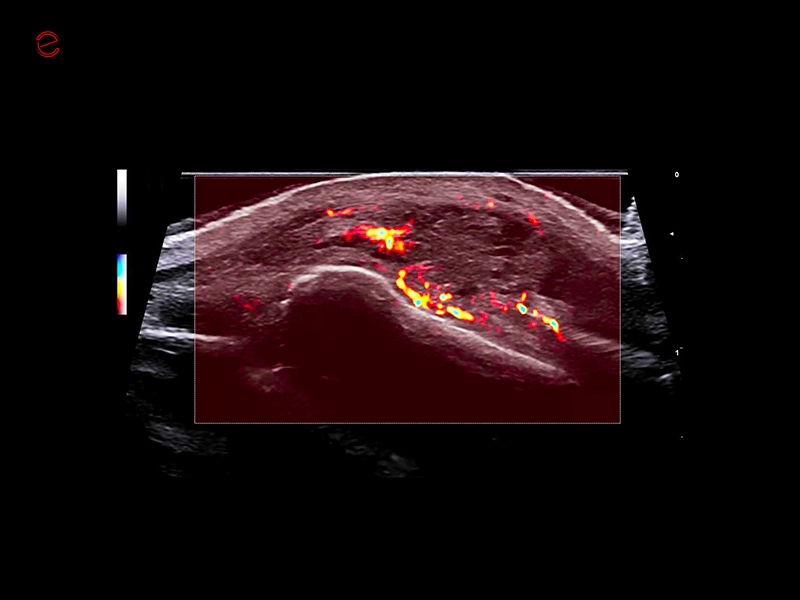

MyLab™C25 - MICRO-V-thyroid-linear

MyLab™C25 - MICRO-V-thyroid-linear